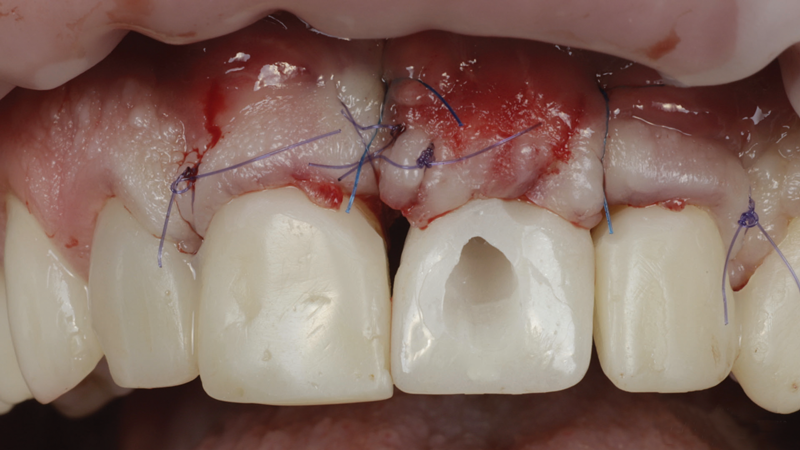

(3.) The crown was removed, and a partial thickness flap was reflected using a papilla-sparing incision design, which revealed that the implant was positioned too far facially and that its body was visible through a very thin layer of bone.

Figure 3

(4.) The crown was removed, and a partial thickness flap was reflected using a papilla-sparing incision design, which revealed that the implant was positioned too far facially and that its body was visible through a very thin layer of bone.

Figure 4

The patient in this case had undergone implant therapy at the site of tooth No. 9 and was restored with a cement-retained restoration more than 5 years prior. At presentation, the site demonstrated a peri-implant soft-tissue dehiscence that extended approximately 3-mm apical to the gingival margin of tooth No. 8. Thin and erythematous marginal tissue was evident at the zenith (Figure 2). The crown was removed, and a partial thickness flap was reflected using a papilla-sparing incision design. This revealed that the implant was positioned too far facially and that its body was visible through a very thin layer of bone (Figure 3 and Figure 4). The first objective of treatment was to minimize the facial extent of the emerging abutment and crown. To accomplish this, the facially positioned abutment and implant crown margin were both recontoured. The second treatment objective was to provide additional supracrestal soft tissue that would more adequately maintain the peri-implant margin. The tuberosity was selected as a donor site due to its dense, high-quality connective tissue, low propensity for shrinkage, and association with minimal patient discomfort. Once the graft was secured (Figure 5 through Figure 7), the flap was coronally positioned (Figure 8). After a healing period of 2 weeks, the margin of tooth No. 9 exhibited an ideal position in relation to its contralateral counterpart and demonstrated increased soft tissue thickness (Figure 9). Three months postoperatively, further healing had improved the esthetics and the position of the margin had been maintained (Figure 10).